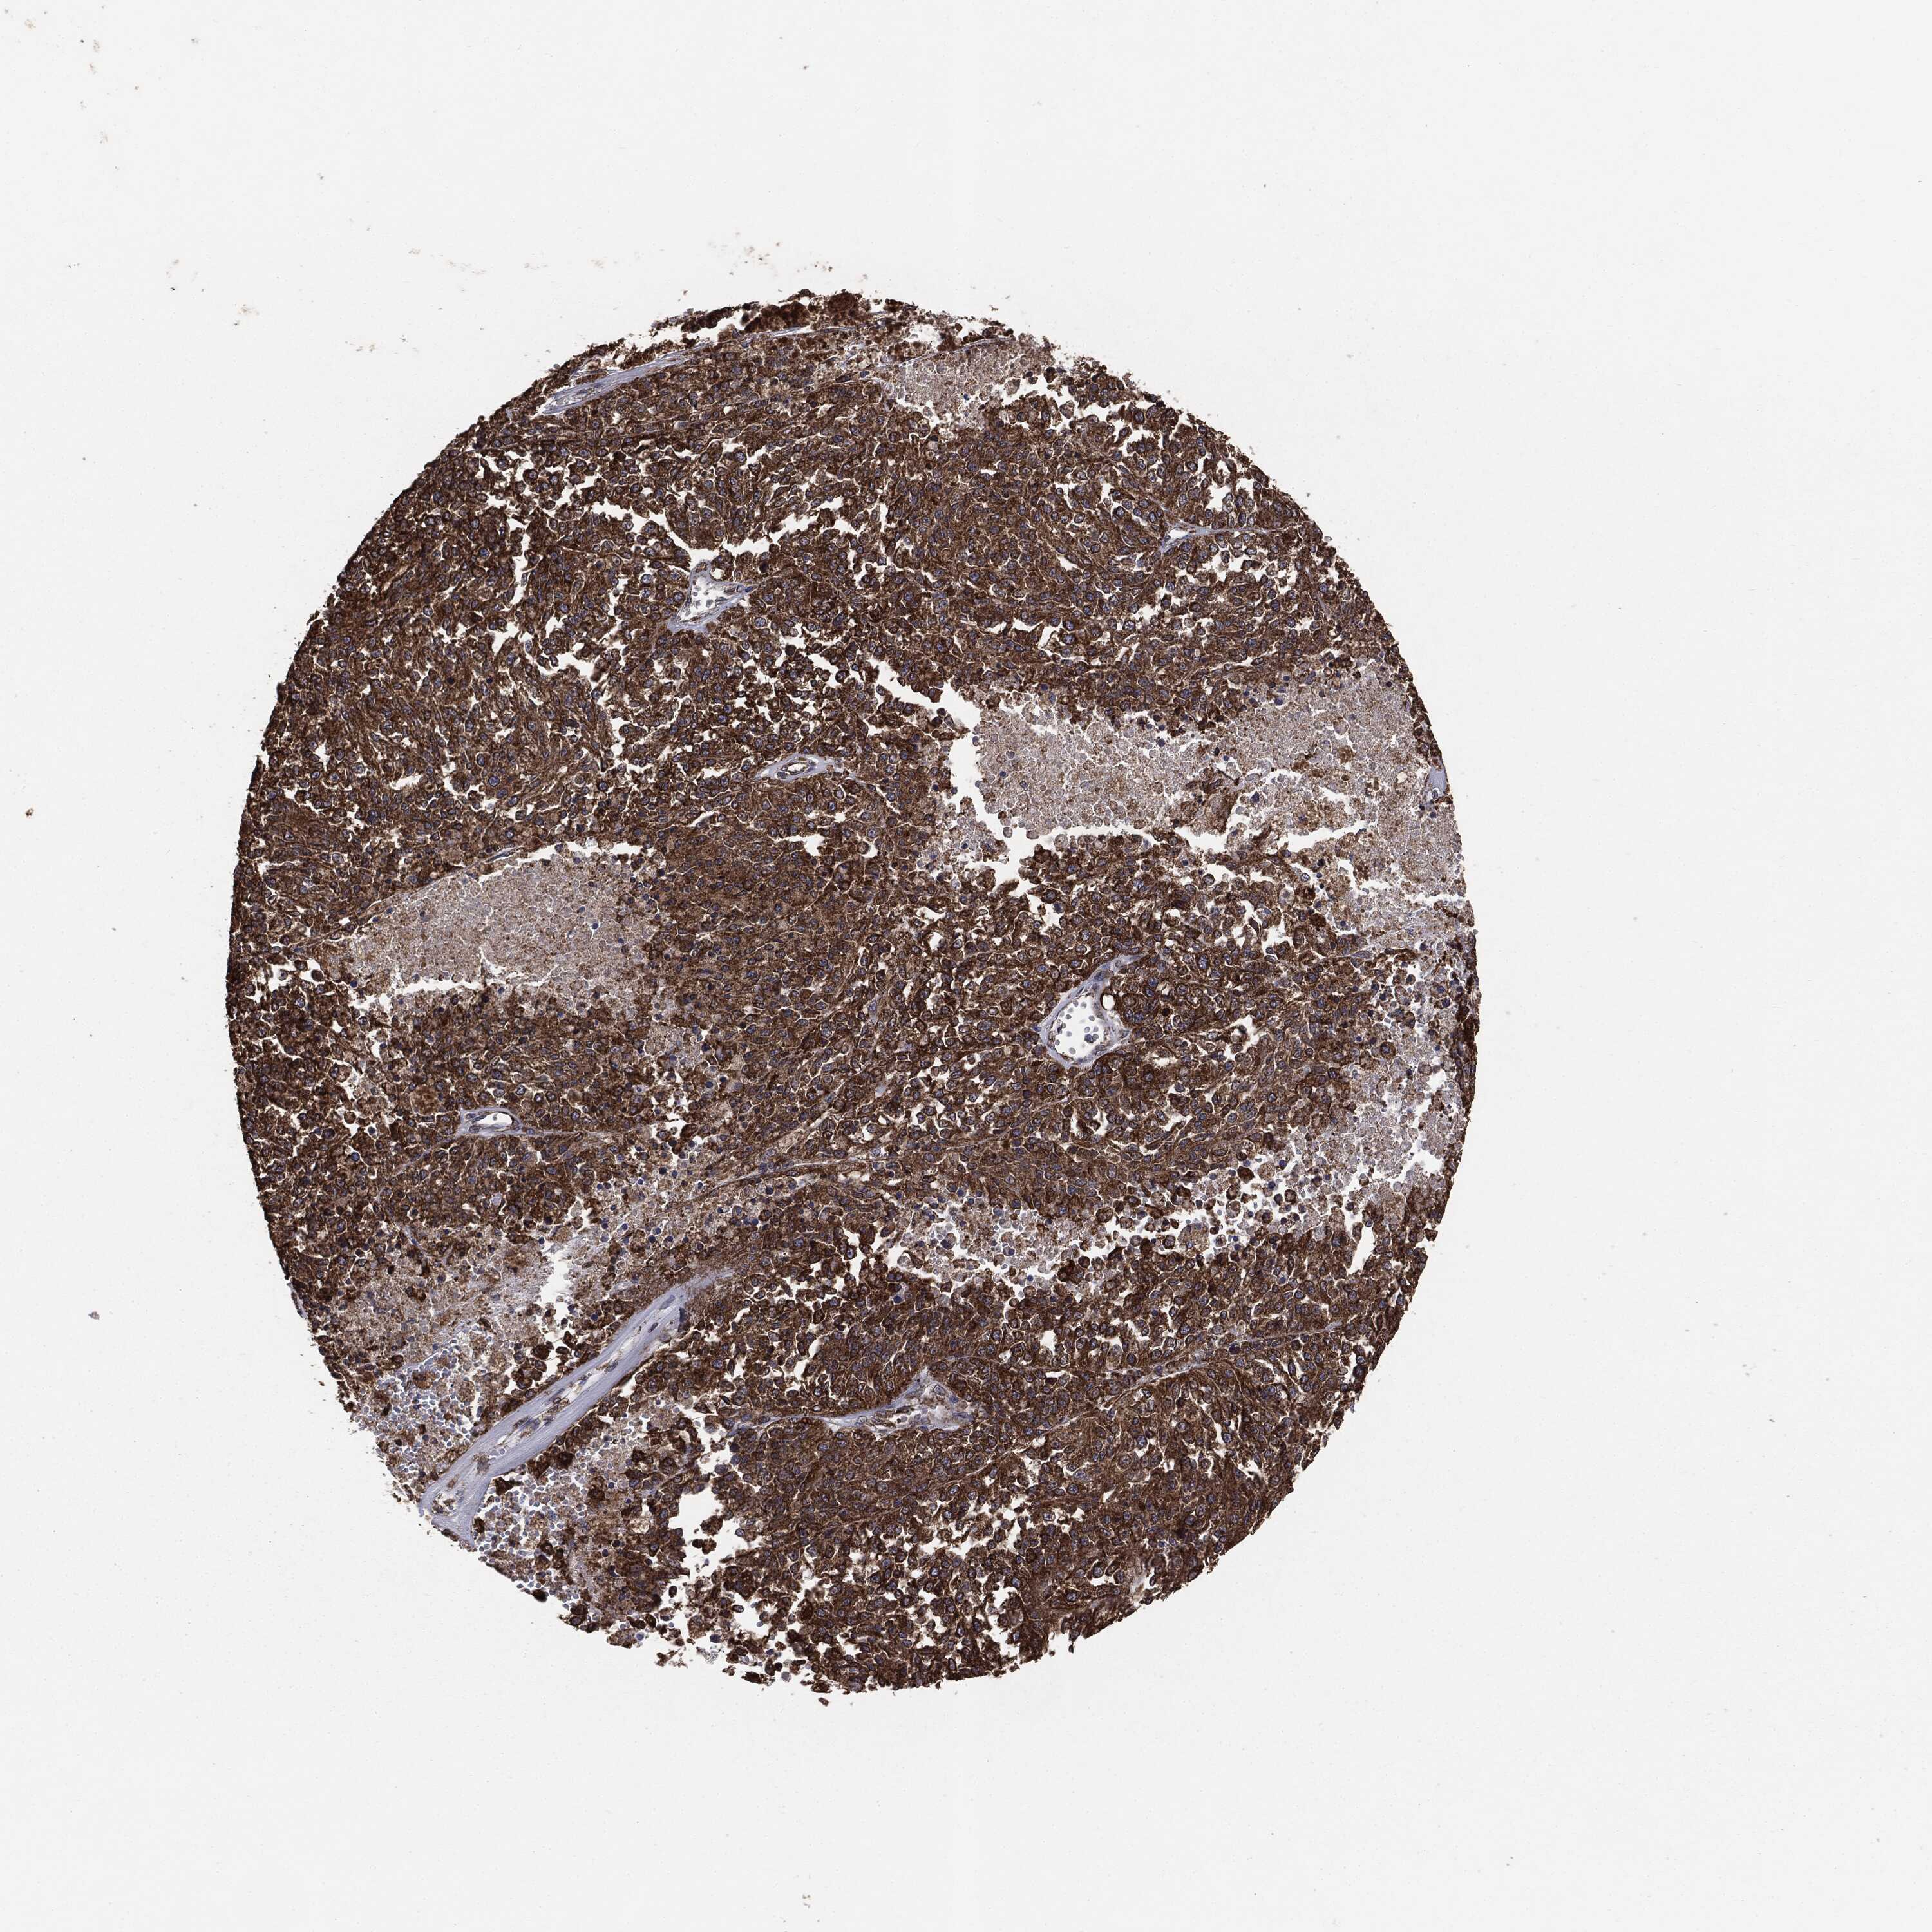

MELANOMA - Protein expressioni

A mouse-over function shows sample information and annotation data. Click on an image to view it in a full screen mode. Samples can be filtered based on level of antibody staining by selecting one or several of the following categories: high, medium, low and not detected. The assay and annotation is described here.

Note that samples used for immunohistochemistry by the Human Protein Atlas do not correspond to samples in the TCGA dataset.

Antibody stainingi

Antibody staining in the annotated cell types in the current human tissue is reported as not detected, low, medium, or high, based on conventional immunohistochemistry profiling in selected tissues. This score is based on the combination of the staining intensity and fraction of stained cells.

Each image is clickable and will lead to virtual microscopy that enables deeper exploration of all samples and also displays staining intensity scores, fraction scores and subcellular localization as well as patient and tissue information for each sample.

Malignant melanoma, NOS

Malignant melanoma, Metastatic site